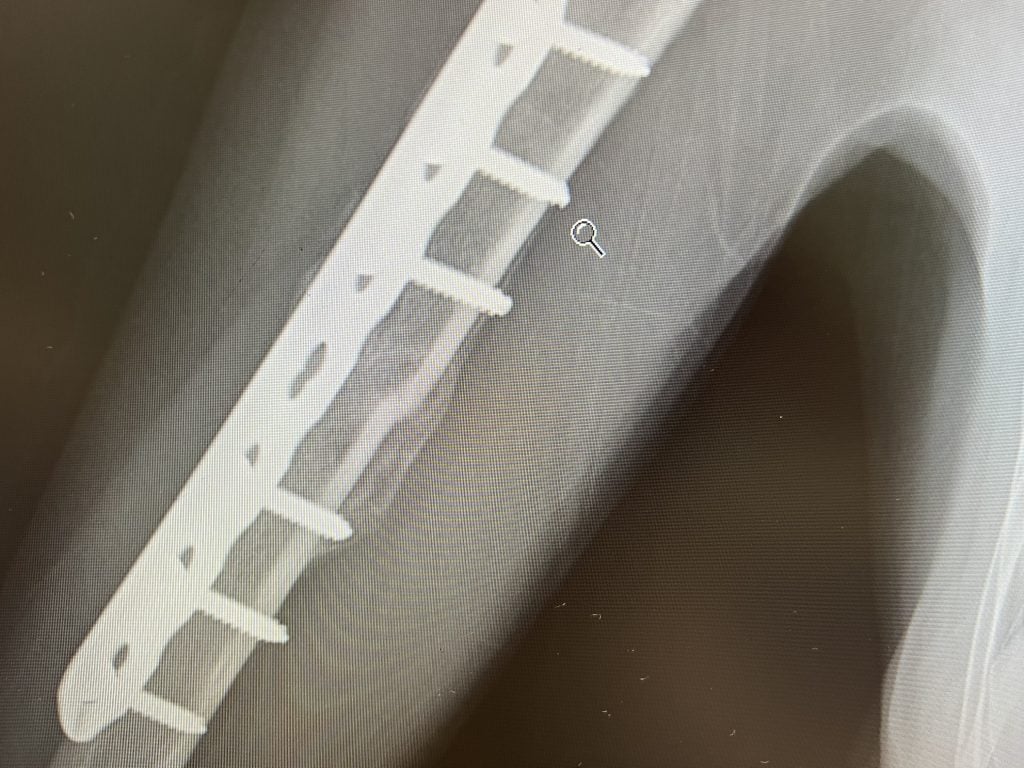

I broke my arm on August 11, 2022 after having a traumatic fall off my horse. I live in Charlotte, NC. After trying to heal naturally for 3 months I was frustrated with my doctor as he couldn’t tell me why I wasn’t able to heal. I then found out about HSS and found Dr. Sama. I had a virtual appointment with him in November 2022. He spent almost an hour on the virtual call with me and my husband. After that appointment I knew that I would have no one but Dr. Sama operate on me. On January 5th he performed an open reduction internal fixation on the transverse fracture of my humerus in my dominant right arm. Today, May 3rd, almost 4 months later I had my final follow up with him. He said that my fracture is officially healed! I’ve been working hard every single day to get both mobility and strength back in my arm. I’m back doing all the activities I love! I cannot thank Dr. Sama enough for everything. He is the BEST!